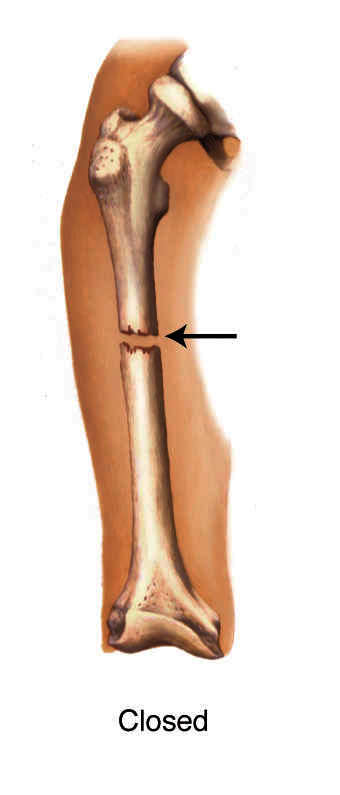

Closed Fracture:

A fracture of the bone with no skin wound.